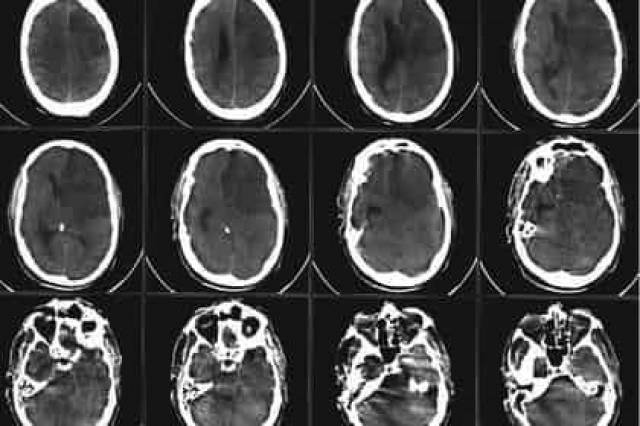

Обычно причиной ишемического инсульта является закупорка кровеносного сосуда в мозге тромбом: кровообращение останавливается, и в результате дефицита кислорода многие нервные клетки умирают, что приводит к нарушениям в работе моторно-двигательного аппарата, органов чувственного восприятия и сознания.

Ученые продемонстрировали, что после искусственно вызванного у мышей инсульта в пораженных участках мозга опорные клетки, так называемые астроциты, начинают превращаться в нервные клетки.